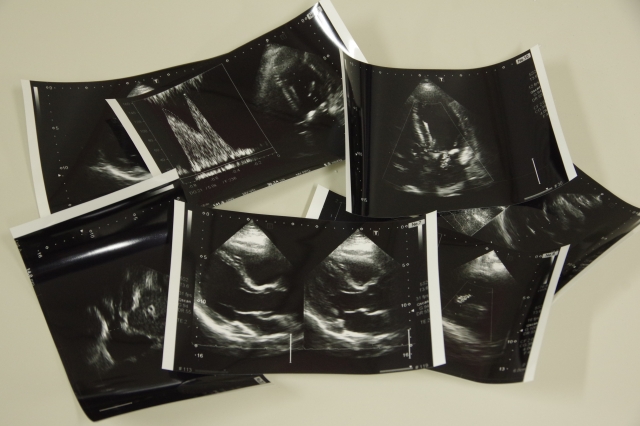

超音波

超音波検査は、痛みもなく体への負担が

少ない安全な検査です。

放射線を使わないので、何度でも安心して受けられます。

また、短時間でしっかりとした診断ができ、

患者さんへの負担をできるだけ軽くしています。

この検査では、リアルタイムで身体の中を確認でき、

検査中も患者さんとお話ししながら進められます。

その日のうちに検査が受けられ、

検査時間は5-10分程度で費用も比較的リーズナブルです。